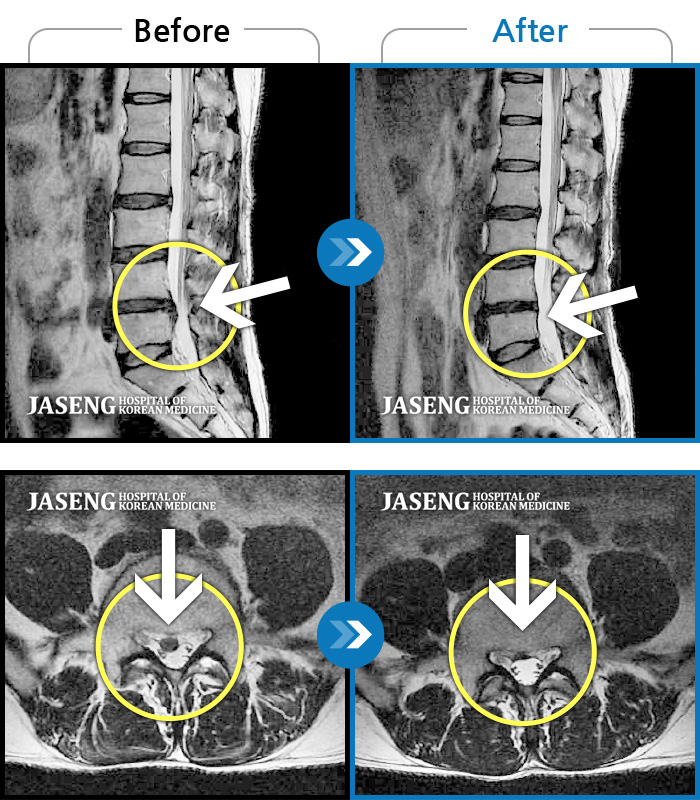

허리디스크

많이 본 사례

수원 · 김태성 원장

허리 통증과 좌측 대퇴부 저림과 당김

촬영시기

2023.02.03 ~ 2024.02.14

2024.11.21